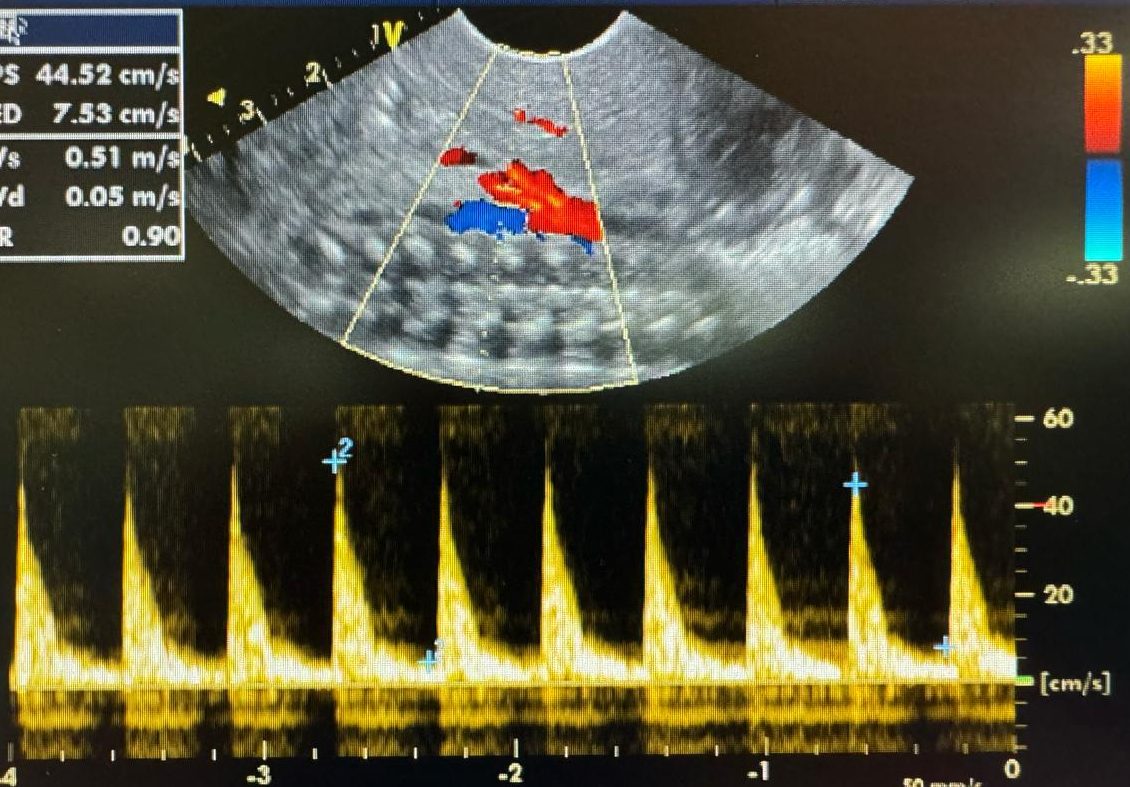

Caracterizada por un engrosamiento anormal del músculo pilórico, lo que lleva a una obstrucción de la salida gástrica. Esta condición es una causa común de vómitos no biliosos en lactantes y generalmente se presenta entre las 2 y 12 semanas de vida.

El diagnóstico se realiza principalmente mediante ecografía, que muestra un alargamiento constante y un engrosamiento de la pared del píloro, con una longitud del canal pilórico superior a 18 mm y un grosor muscular de al menos 4 mm.

Ejemplos de estenosis pilorica hipertrofica infantil.